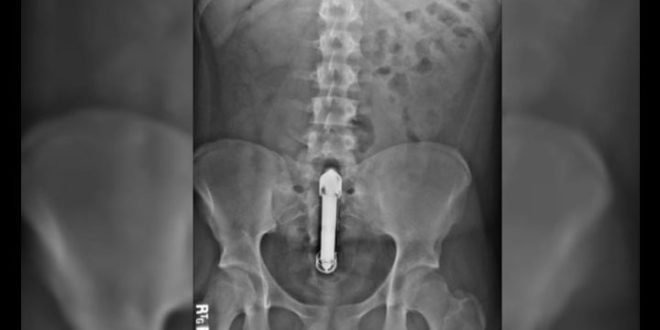

Un hombre, de unos 50 años y totalmente desnudo, vivió momentos críticos luego que un consolador se le trabara en su trasero. El hecho se registró en Avenida Balbín y Crisólogo Larralde, Argentina.

Según los testigos, el hombre salió a la calle desnudo pidiendo ayuda a gritos.

Con la policía presente, el individuo que aparentaba algún desorden mental, pedía que se llame a los médicos, mientras esbozaba gritos de dolor. Además, hacía ademanes para intentar sacarse el artefacto por sus propios medios.

Se desconoce de dónde apareció y si el accidente se dio en soledad o como parte de la relación con un tercero. Finalmente, el individuo consiguió ayuda en un enfermero.